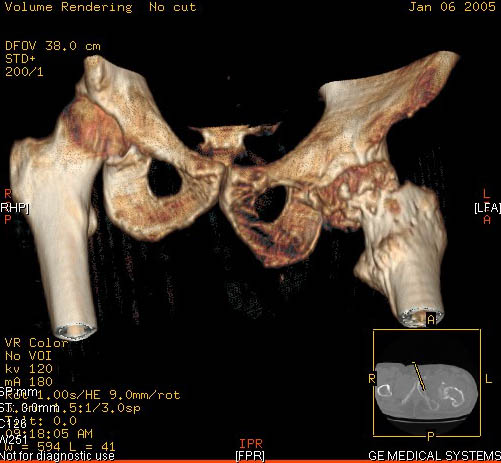

И снова вопрос по эндопротезированию: Пациенту 51 год. Болен с 2000 г, когда отметил умеренные, нараостающие боли в в/3 левого бедра, прогрессирующую контрактуру лев Т/Б сустава.

05.12.04 после падения на бедро боли резко усилились, нога стала неопорной. На рентгенограмме обнаружен патологический перелом шейки бедренной кости. Обследован в отделении костной онкологии. Результат биопсии: асептический некроз проксимального отдела бедренной кости. Вопрос: выбор технологии эндопротезирования - цементная или бесцементная версия. Заранее благодарю! С уважением,А.В.Владзимирский

Проксимальный отдел бедра не виден достаточно на представленных рентгенограммах; но то, что видно, как раз наводит на мысли о цементной фиксации - цилиндрический канал, измененный calcar, кистозные изменения в области большого вертела и т.д.

Evgueny Tchekashkine 01 Февраль 2005, 04:15

Как то очень подозрительно выглядит проксимальный отдел бедра для такого очень простого гистологического заключения. Вы уверены, что гистология настолько благополучна и в каком варианте она выполнялась: пункционная или открытая с забором костного блока? Не уверен на все сто , но область проксимального отдела бедра - одно из излюбленных мест для гигантоклеточной опухоли, которая зачастую озлакочествляется (имел два подобных наблюдения). Из своей практики могу сказать, что, к сожалению, информативность пункционной биопсии не сравнима с открытой техникой. Поэтому прежде чем решать цементный или бесцементный протез использовать, я бы повторил биопсию в сочетании со сканированием скелета, сывороточная щелочная фосфатаза, кальций, фосфор сыворотки, СОЭ, С- реактивный белок,

Soglasen s Евгений И Чекашкин, proximal Femur does not look right. Sarcoma? Pagets, Osteomyelitis?. Technicality of the implantaion will be dependent upon underlying pathology, and the surgeon's level of comfort.

Действительно, проксимальный отдел бедра выглядит подозрительно. По-моему напоминает болезнь Педжета. Кстати, гистологическое заключение в таком случае часто звучит как "хроническое воспаление", "асептический некроз с элементами лейкоцитарной инфильтрации" и т.п. Далеко не все патоморфологи имеют достаточный опыт для дифференцировки костной патологии.